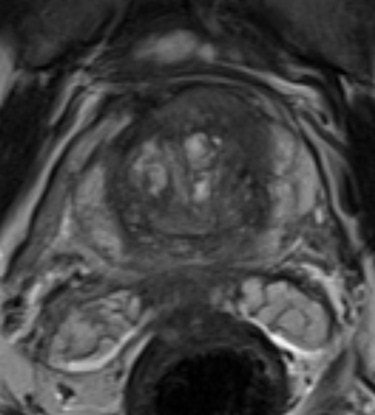

Computer-aided diagnosis (CADx) shows potential as a tool to aid radiologists in the challenging task of finding cancer originating from the prostate's central gland, according to Dutch research presented at the 2012 RSNA meeting in Chicago.

In a study of the institution's CADx system on 101 patients, researchers from Radboud University Nijmegen Medical Center's Diagnostic Image Analysis Group found the software yielded similar performance to that achieved by radiologists in a prior study in the literature.

Seventy percent of prostate cancers originate in the peripheral zone of the prostate, while 30% come from the central gland; as a result, most clinical and CAD research in prostate MRI focus on the peripheral zone. However, central gland lesions are difficult to diagnose on MRI, Litjen said.

Because the recently published Prostate Imaging Reporting and Data System (PI-RADS) described texture characteristics as the most important feature in detecting cancer in the central gland, the researchers decided to develop a CADx system to differentiate between normal/benign and malignant areas using texture and relaxation features, Litjens said. Relaxation features (T2 maps) are needed due the lack of standardization in MR signal intensity.

"Our results show that an area under the [receiver operator characteristics (ROC)] curve of 0.76 can be achieved using our method, which is similar to the performance of radiologists reported in literature when they only have T2-weighted images available," Litjens said.